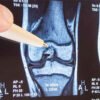

Arthrofibrosis is a complex and often misunderstood condition that can occur after knee surgery, particularly after total knee replacement (TKR) , ACL reconstruction, or manipulation under anaesthesia (MUA). It involves excessive scar tissue formation, leading to stiffness, pain, and reduced range of movement (ROM). For many patients, this condition can be frustrating and debilitating limiting recovery and impacting quality of life.

Arthrofibrosis occurs when the body overproduces fibrous scar tissue in response to injury or surgery. While some scar formation is normal and part of healing, excessive or disorganised scar tissue can restrict joint movement and cause persistent pain.

At a biological level, arthrofibrosis involves an overactive wound healing response. After surgery, fibroblasts (cells that produce collagen) and myofibroblasts (specialised cells that contract and remodel tissue) become activated. In arthrofibrosis, these cells remain active longer than necessary, laying down excessive collagen and causing contractures.